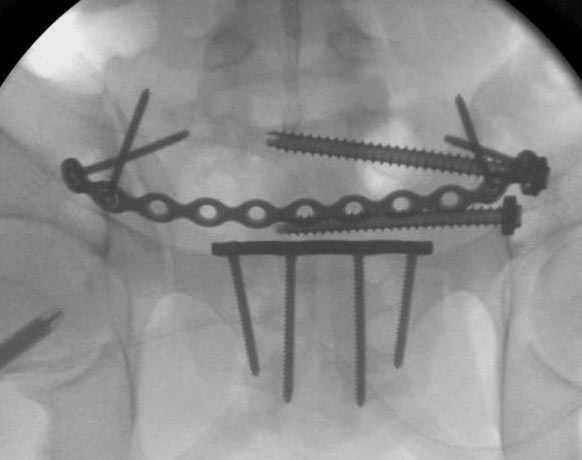

Здесь слайды случая больного с политравмой, включающей сегментарный перелом бедра и повреждение таза с нарушением тазового кольца, разрыв симфиза и перелома крестца зон 2 и 3.

На множественных слайдах важные моменты операции. Хотел бы подчеркнуть, как важно иметь возможности всех необходимых ренгенограмм, включая компютерную томографию и стандартных внутритазовых рентгенограмм (инлет и оутлет).